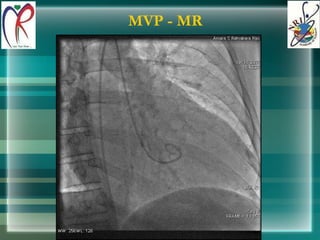

MVP - MR